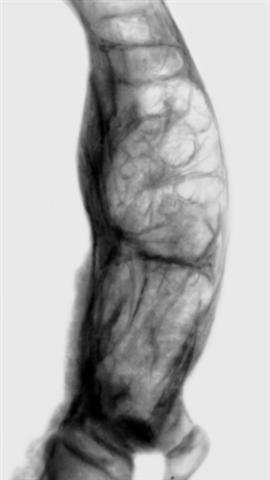

Рис. 2. Рентгенограмма дистального конца деформированной левой бедренной кости при болезни Педжета.